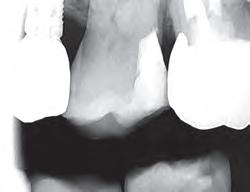

An astringent is a substance that eliminates permeability of epithelium to tissue fluid flow. The result is a dry field, an important tissue management solution. An ideal impression for successful crowns, veneers, and bridges must accurately capture the preparation margins. This can be ensured only through reliable hemostasis and gingival displacement.

1. Subgingival preparation with bleeding. BLEEDING HEMOSTASIS

2. Scrub Astringedent™ X hemostatic firmly against bleeding tissues with Metal DentoInfusor™ tip.

CLEANING/TESTINGDISPLACEMENT

3. Firm air/water spray removes residual

and tests tissue for quality, profound hemostasis.

Remove

4. Soak Ultrapak™ knitted cord in Astringedent™ X hemostatic, pack, and leave for 5 minutes.

7. Predictable quality impressions. RESULT